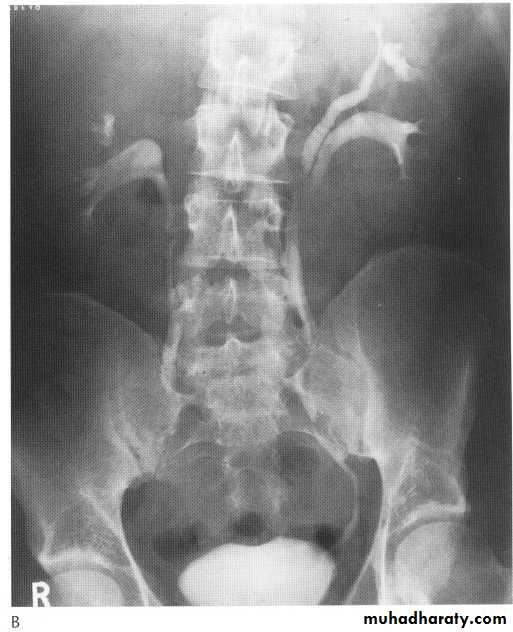

bilateral small kidney

generalized arteriosclorosis

Chronic glumerlunephritis

Chronic papillary necrosis

arterial hypotension

bilateral causes of unilateral kidney